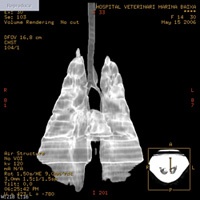

Tórax: